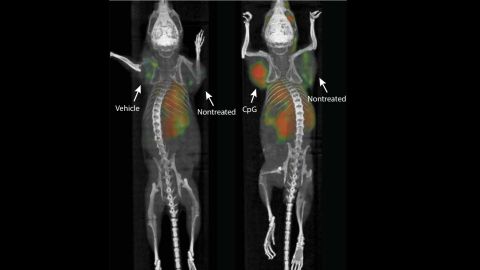

Después de inyectar una combinación de dos refuerzos inmunes directamente en tumores sólidos de ratón, el equipo de investigación ha asegurado que la vacuna ha conseguido eliminar todos los rastros del cáncer específico del cuerpo del animal, incluidas las metástasis que no se habían tratado previamente.

El experimento se replicó en otros 90 ratones y logró erradicar los tumores en 87 de ellos, lo que permitió a los investigadores declararlos libres de cáncer. El cáncer recurrió en tres de los animales, pero los tumores retrocedieron luego de otra ronda de tratamiento inmunológico. El estudio también fue exitoso en ratones que tenían tumores de mama, colon y melanoma.

A diferencia de otros tratamientos contra el cáncer ya en el mercado, este método ha anulado la necesidad de infiltrarse en el sistema inmunitario completo del animal o utilizar muestras de su cuerpo. "Nuestro enfoque utiliza una sola aplicación de cantidades muy pequeñas de dos agentes para estimular las células inmunes solo dentro del tumor. En los ratones, vimos efectos increíbles en todo el cuerpo, incluida la eliminación de tumores en todo el animal", explica Levy.